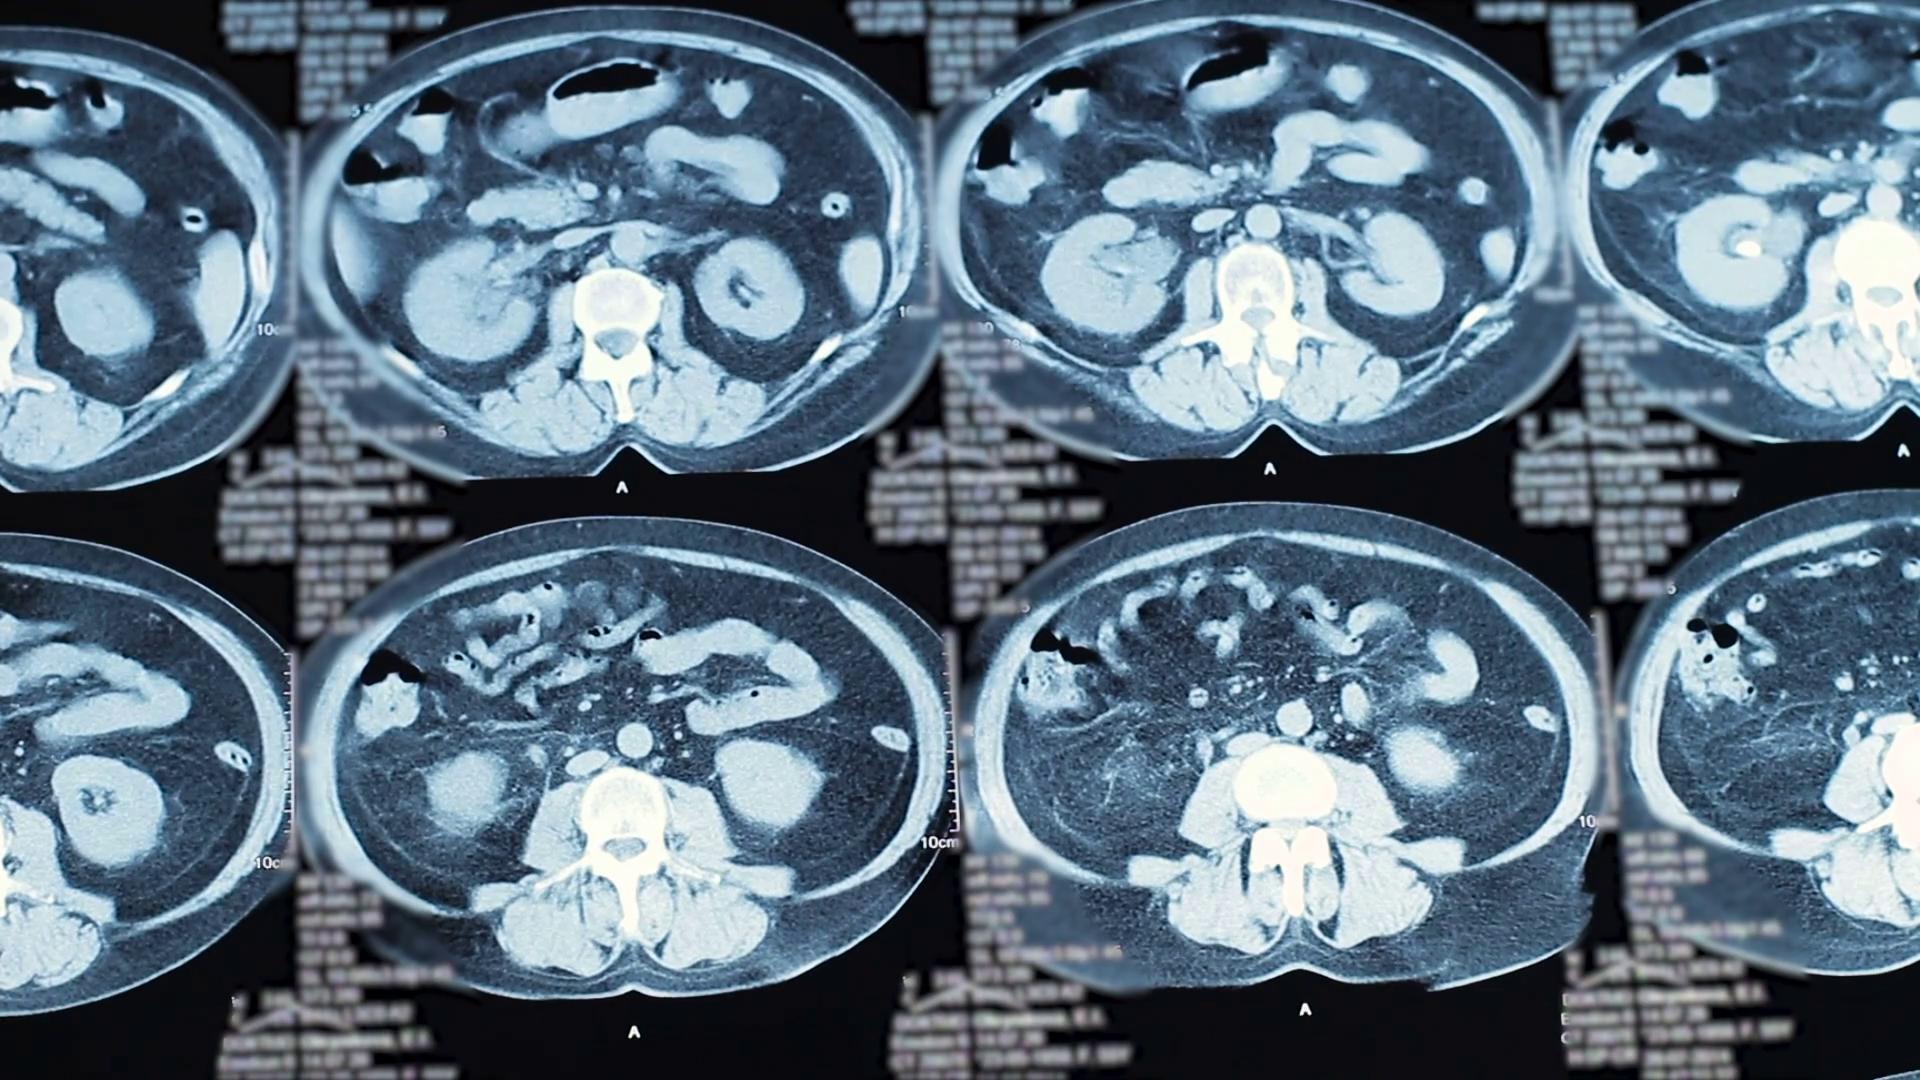

resonance imaging. stones in the kidneys. Close up Stock Video Radiolucent Stones What are the primary causes of radiolucent gallstones? Distal ureteral stones may be manifested by bladder instability, urinary frequency, dysuria and/or pain radiating to the tip of the penis, or the labia or vulva. Patients may present with the classic symptoms of renal colic and hematuria. Others may be asymptomatic or have atypical. The lifetime incidence of renal stones is. Radiolucent Stones.